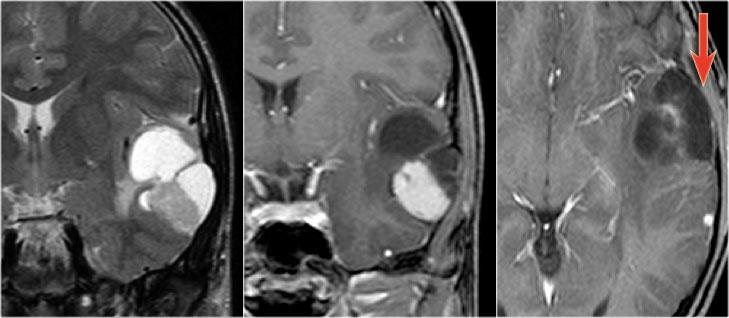

Hình ảnh T2W và FLAIR mặt phẳng coronal cho thấy xơ cứng thùy thái dương trong bên phải.

Lưu ý tình trạng mất thể tích, biểu hiện của teo não, gây giãn thứ phát sừng thái dương của não thất bên.

Tín hiệu cao trong hải mã phản ánh tình trạng gliosis.

Hình ảnh cho thấy xơ cứng thùy thái dương trong với hải mã tăng tín hiệu và teo nhỏ (mũi tên đỏ), kèm theo giãn thứ phát sừng thái dương trái của não thất bên trái.

Cũng cần lưu ý tình trạng tăng tín hiệu dưới vỏ não kết hợp ở thùy thái dương trái, gợi ý loạn sản vỏ não khu trú.